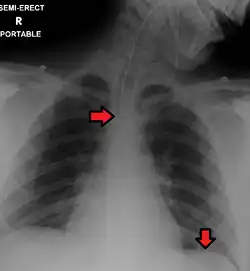

Top Arrow: Endotracheal tube Bottom Arrow: Nasogastric tube

It is necessary to confirm placement of the endotracheal tube to ensure that the tube is properly positioned within the trachea and has not accidentally passed into the esophagus instead. Additionally, it is important to confirm that the endotracheal tube was not placed too deep in the trachea where is may only be ventilating one of the lungs due to it being positioned within a mainstem bronchi (frequently the right mainstem bronchi due to a more obtuse angle than the left). The gold standard for confirming successful placement of an endotracheal tube is direct visualization of the tube passing through the vocal cords and positive end-tidal carbon dioxide on capnography. Secondary methods of confirmation include oxygen saturation, chest x-ray, ultrasound, condensation in the endotracheal tube, equal chest rise, breath sounds heard on both sides of the chest (often with the assistance of a large tidal volume breath), and an absence of breath sounds over the epigastrium. No single method of confirming placement is 100% reliable so multiple methods of confirmation should be utilized.[6][17][18]